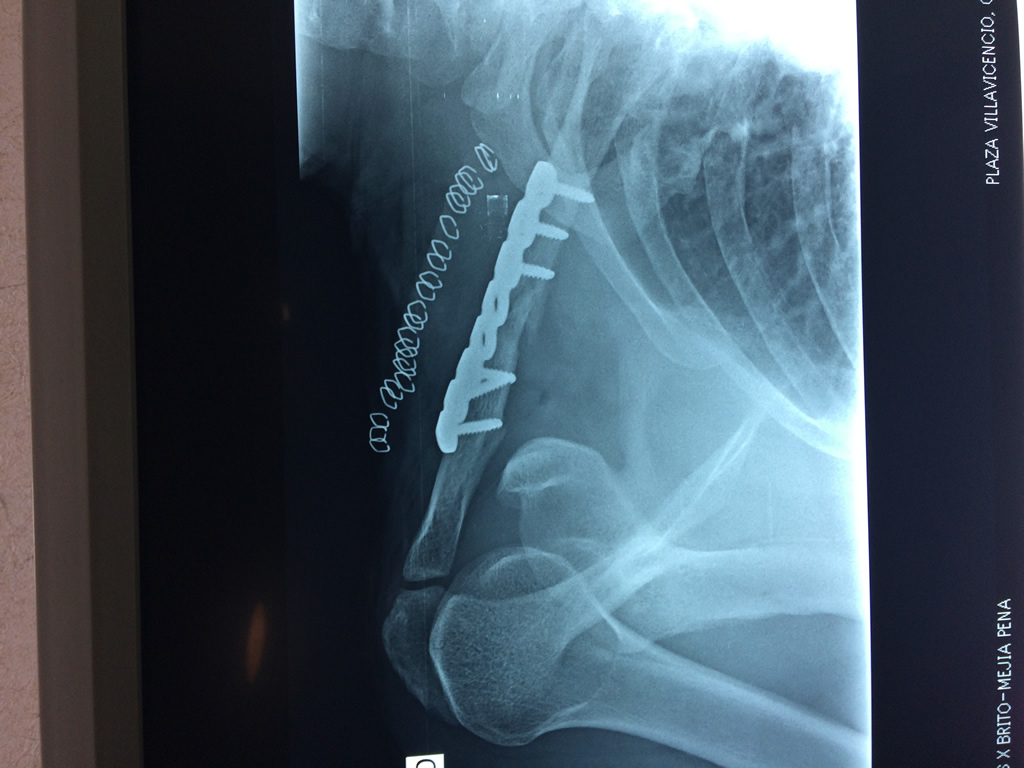

Clavicula 2

Detail Download